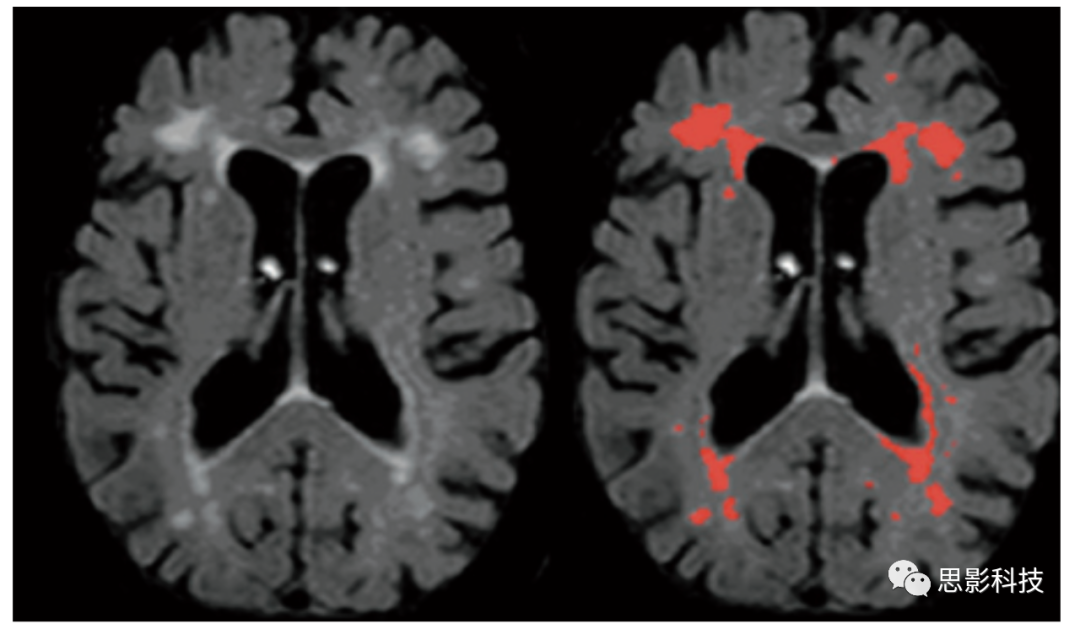

WMH有時被稱為腦白質疏松或腦白質病,表現(xiàn)為T2高信號。大量臨床和老化研究中對WMH進行了豐富研究,并存在較多爭議,一部分認為WMH是偶然的無臨床意義,一部分認為WMH是認知、運動和情緒功能障礙的主要來源。最初,WMH被描述為“不明原因亮點(unidentifiable bright objects)”,放射醫(yī)師混淆其為人工來源或者老化伴隨產物。實際上,年齡與WMH嚴重程度的相關性最強,大多數(shù)老年人均存在WMH負擔。圖1展示了典型廣泛分布WMH,圖22例老年人,一例為輕度WMH,一例是更為嚴重WMH。WMH通常出現(xiàn)在側腦室周圍的白質(如:“室周”WMH),向深部白質和灰質核團深入(深部”WMH),或作為皮層深部組織中有邊界的點狀球體。值得注意的是,點狀WMH常孤立出現(xiàn)在MRI軸位面,但在三維重建中,通常在同側側腦室同一主干分布。

老年人腦白質高信號嚴重程度的最優(yōu)表征一直備受爭議。部分研究人員認為室周WMH在臨床中不如深部WMH重要。部分研究人員強調了WMH區(qū)域及分布的重要性。這些特征反映在許多視覺評分量表中,例如Scheltens量表,評估WMH的嚴重程度和分布的常用方法。本實驗室開發(fā)了一種局部WMH嚴重程度分析的定量方法。簡單地說,通過考慮每個被試FLAIR圖像的體素強度分布,將高斯曲線擬合到每個大腦半球,并推導出每個半球的均值和標準差,WMH種子點被定義為高于或等于平均值2.5倍標準差。左邊和右邊的種子點被合并,然后每個種子點被傳遞到一個基于平均強度的局部生長算法。該算法使用種子點體素強度作為其起始平均值,并應用10點連接方案(x-y平面,1個在z平面上,1個在z軸下),搜索并標記落在種子均值5%以內的體素。相鄰體素信號下降低于5%被添加到圖像中,并創(chuàng)建一個新的平均值。該過程不斷迭代,直到所有種子都包含在最終的WMH圖像中。標記為WMH的體素數(shù)量乘以體素維度得到WMH總體積。通過對每張圖像進行空間標準化至解剖圖譜,可得到主要解剖腦葉、基底節(jié)區(qū)及小腦WMH體積。圖3展示了FLAIR圖像三個正交視圖,其中標記WMH并進行局部分割。此外,通過對側腦室分割(圖4),可以計算每個體素至側腦室壁的三維距離。因此,該定量處理方法可以用來導出WMH的總體積、局部WMH體積,以及室周和深部WMH體積。